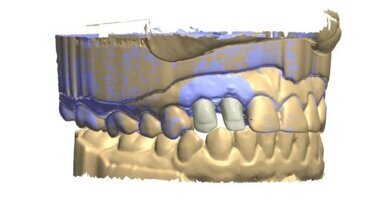

55-letni pacjent, po odbudowie odcinków bocznych mostami ceramicznymi w sposób klasyczny, zgodził się na zastosowanie cyfrowych technik rejestracji celem wykonania odbudowy protetycznej odcinka przedniego (Ryc. 3). Po wykonaniu preparacji filarów: 13, 12, 11, 21, 22 i 23 zarejestrowałem cały łuk górnych zębów za pomocą skanera wewnątrzustnego (Ryc. 4). Następnie dokonałem rejestracji całego łuku dolnych zębów (Ryc. 5).

Kolejnym etapem jest zarejestrowanie okluzji. W tym celu prosimy pacjenta o zagryzienie zębów i skanujemy grupę 2-3 zębów dolnych wraz z przylegającym do nich dziąsłem oraz grupę 2-3 zębów przeciwstawnych(górnych), także z przylegającym dziąsłem.Skaner automatycznie składa zeskanowane wcześniej łuki górny i dolny w prawidłowym okluzyjnym położeniu (Ryc. 6).

Szybkie, wygodne dla pacjenta, cyfrowe zarejestrowanie warunków w jamie ustnej daje bezpośredni dostęp do trójwymiarowego obrazu (Ryc. 16-18). Dzięki temu możemy przeprowadzić wstępną analizę łuków zębowych w różnej projekcji i w różnym powiększeniu, obraz na ekranie skanera można powiększać i obracać. W klasycznym postępowaniu taka analiza możliwa jest dopiero po kilku godzinach. Na ekranie skanera możemy skorzystać z funkcji rysowania linii. W oparciu o linie pionowe (zielone linie na rycinach) uzyskujemy informację o prawidłowej preparacji zębów (Ryc. 19 i 20).